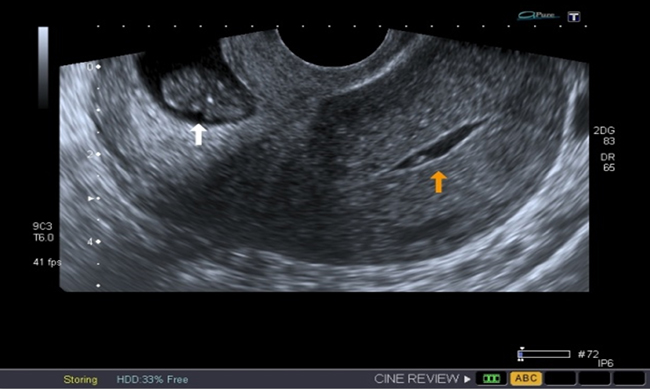

A la paciente se le realizó una prueba en sangre para cuantificar la fracción beta de la gonadotrofina coriónica humana (Abbott Laboratories. Architect.B-hCG Total), que se reportó en 31.819 mUI/ml. También se le tomó una ecografía endovaginal (Toshiba-Xario XG) que mostró la presencia de útero con medidas de 72 × 52 × 54 mm con un cuello de 35 mm con orificio interno cerrado. El endometrio midió 18 mm, sin evidencia de saco gestacional intrauterino y en la región ístmica y cervical, por debajo de las arterias uterinas, se encontró un saco gestacional de 30 mm con presencia de embrión único de 20,6 mm sin presencia de actividad cardiaca fetal (figuras 1 a 4).

Figura 2 Presencia de cavidad endometrial vacía (flecha amarilla). Embarazo extrauterino cervical con embrión único sin actividad cardiaca (flecha blanca)